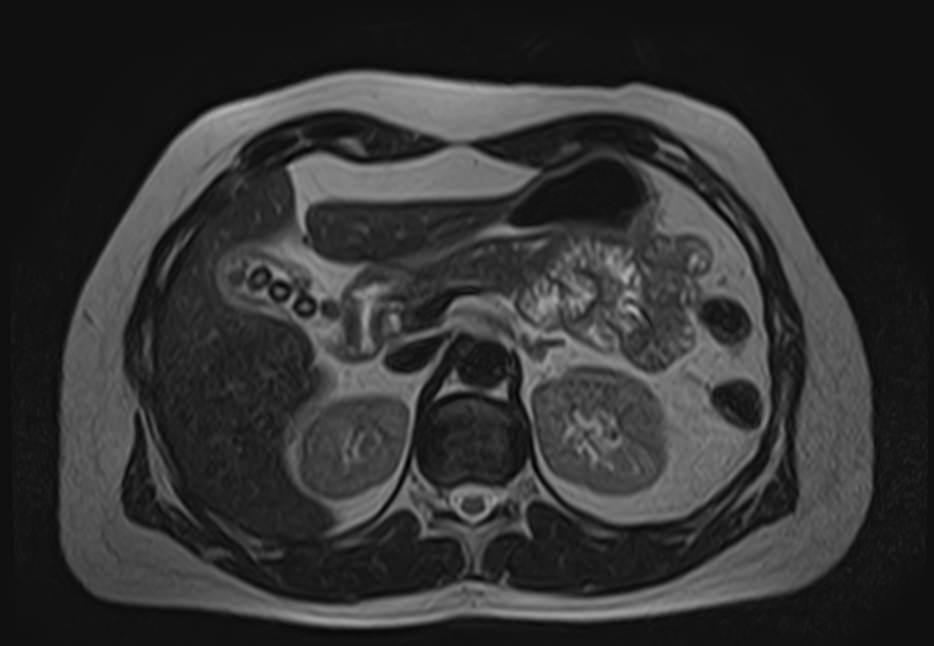

МРТ забрюшинного пространства является наиболее информативным, безопасным и доступным методом исследования, который позволяет оценить состояние органов, расположенных в данной анатомической зоне (почки, надпочечники, мочеточники), выявить возможные патологические процессы.

В клинике «Доступная медицина» установлен новейший высокопольный томограф экспертного уровня TOSHIBA VANTAGE TITAN 1,5 Тесла, на котором выполняется обследование органов забрюшинного пространства. За счет высокой индукции магнитного поля аппарат при сканировании создает изображения на плоскости превосходной четкости, затем с помощью компьютерных приложений данные преобразуются в изображения трехмерного формата, что обеспечивает точность и достоверность диагностики.

МРТ брюшного и забрюшинного пространства направлено на определение состояния нескольких органов, по результатам диагностики визуализируют:

- Почки. С помощью магнитно-резонансной томографии удается диагностировать структурные изменения. Аномалии развития, воспалительные процессы, изменение нормального расположения в забрюшинном пространстве.

- Надпочечники. Парный орган эндокринной системы. Из-за особенностей анатомии, строения, трудно визуализируются прочими способами. МРТ позволяет получить детальную картину изменений надпочечников.

- Аорта и нижняя полая вена. В рамках диагностики структурных патологий.

- Мочеточники. Часть мочевыделительного тракта. Из-за малого диаметра и особенностей строения, визуализируются с трудом. Томография — основной способ диагностики патологических процессов.